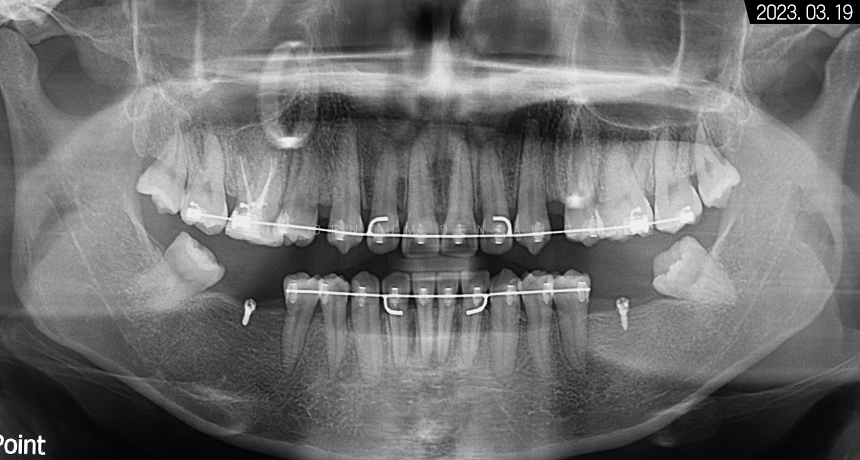

그래서 우선 파노라마 엑스레이 촬영으로

전체적인 구강 환경을 살펴봤는데요.

전치부는 과잉 밀집으로 몰려있는 것이 보였고

위턱은 사랑니까지 맹출 되어

아주 빽빽한 치열을 갖고 계셨습니다.

아래턱은 어금니 상실 부위가 여러 군데여서

식사가 불편하셨을 것으로 예상되었습니다.

어금니는 저작할 때 아주 중요한 부위이기 때문에

그 부위가 사라지면

단단한 음식을 씹는 것도 용이하지 않고

전치부에 힘이 몰려

앞니 파절과 마모도 야기할 수 있으며

오랜 기간이 지나면 맞은편

어금니 정출 현상도 나타날 수 있기 때문에

가급적 제기능을 할 수 있도록

치료하는 것이 좋습니다.